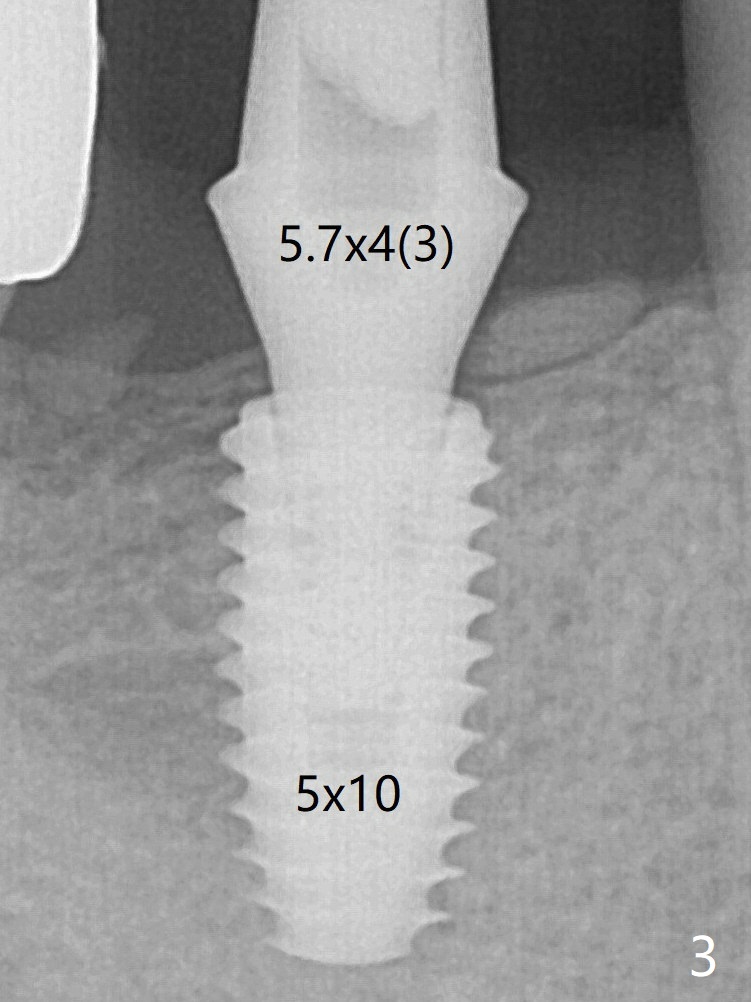

The 5x10 mm implant placed with guide has good trajectory and depth in a timely manner (Fig.3). Since the patient is a heavy bruxer with dislodgement of #30 provisional and #19 abutment screw loosening, a 5.7x4(3) mm cementation abutment is placed immediately so that a splinted provisional is fabricated for #30 and 31 for better retention. However, the gingiva around the implant at #31 is unhealthy 3 months postop (Fig.4). After impression, the provisional at #31 is sectioned without recementation for better oral hygiene.